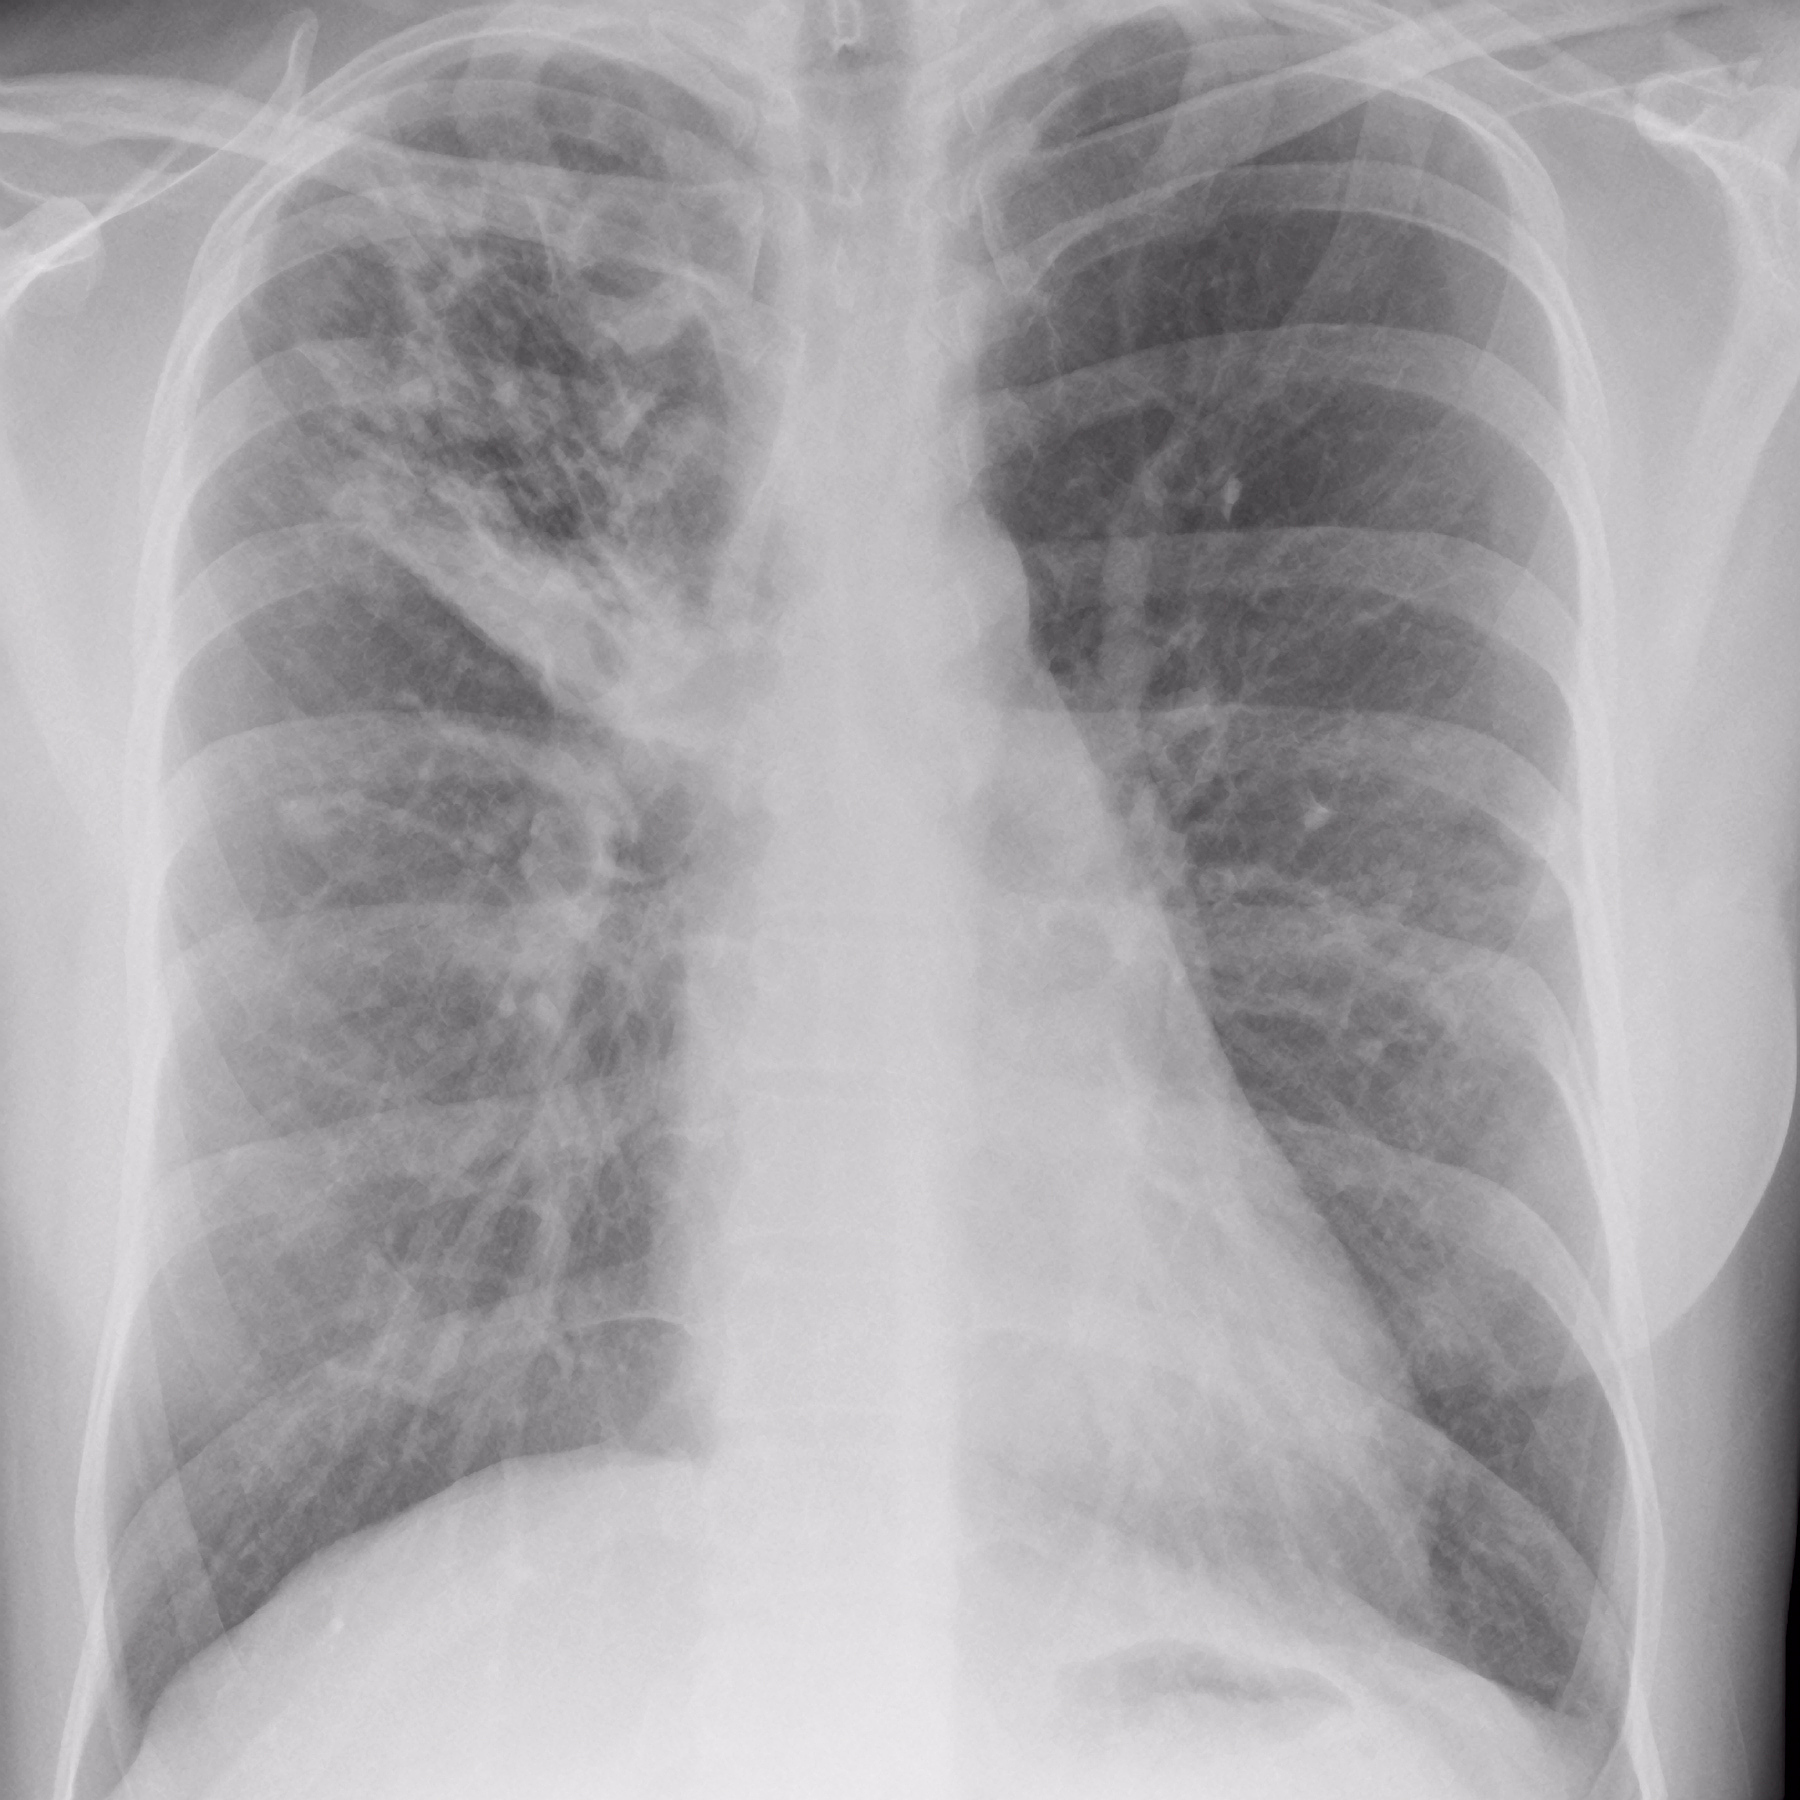

结核病是一种由结核分枝杆菌引起的慢性传染病,影响了人类数千年。以下是其发展历程:

6. 21世纪:尽管结核病的治疗方法不断改进,但该疾病仍然是全球最大的健康威胁之一,每年仍有数百万人死于结核病。全球各地的政府和组织努力控制结核病的传播,通过预防接种、筛查和治疗,以期实现结核病的消除。